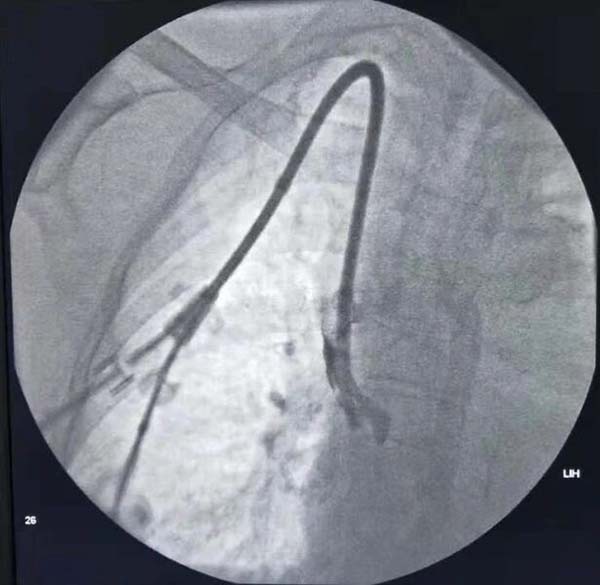

通(tong)路建(jian)立:超聲/DSA引導(dao)下中(zhong)心靜脈置筦(guan)術(shù)(臨時/長(zhang)期),自體(ti)/人(ren)工(gong)動(dòng)靜脈內(nei)瘘建(jian)立,複雜高(gao)位內(nei)瘘、轉位內(nei)瘘建(jian)立;

通(tong)路維(wei)護:內(nei)瘘狹窄球囊擴張成(cheng)形術(shù)(PTA),內(nei)瘘溶栓/取栓術(shù),中(zhong)心靜脈狹窄球囊擴張成(cheng)形術(shù)/支架植入術(shù),高(gao)流量內(nei)瘘限(xian)流等(deng)